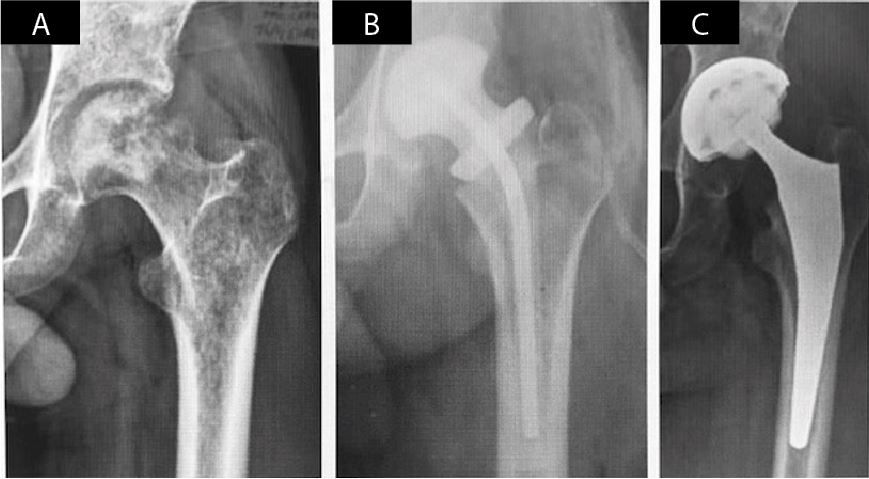

The issue's clinical contributions center on the diagnosis and management of orthopedic infection. Epidemiological and microbiological dimensions are addressed through a 5-year retrospective investigation of septic arthritis of the knee in Azerbaijan, complemented by therapeutic guidelines for joint arthroplasty in sequelae of septic hip arthritis. Operative strategies including static spacers in periprosthetic knee infections, antibacterial implant coating, and a novel DTT-based diagnostic approach to biofilm-related infections further define the issue's scientific scope.